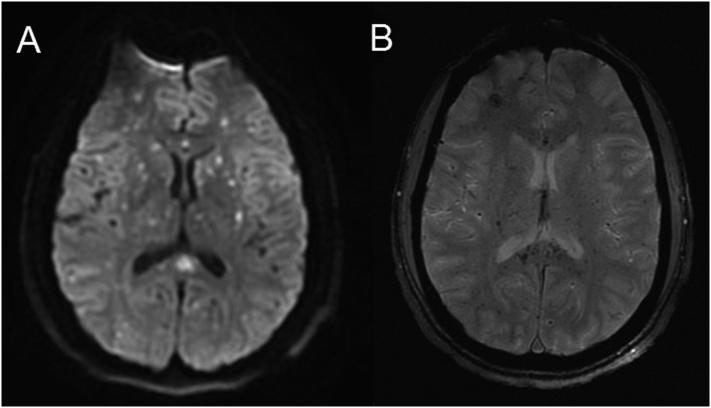

Fat embolism syndrome (FES) is a known complication of sickle cell disease (SCD) that occurs secondary to vaso-occlusive crises, bone marrow infarction, and the subsequent release of fat globules into the venous circulation. Although neurologic involvement is common, the pathophysiology of cerebral fat emboli remains controversial. While fat microemboli can enter the arterial circulation through right-to-left shunts, the systemic release of free fatty acids may also cause indirect endothelial damage and disruption of the blood-brain-barrier. We present an unusual case of cerebral fat emboli in SCD that occurred in the absence of acute chest syndrome or right-to-left shunt, favoring a biochemical etiology. Treatment of FES includes supportive care and emergent red cell exchange transfusions.

脂肪栓塞综合征(FES)是镰状细胞病(SCD)的一种已知并发症,继发于血管闭塞性危机、骨髓梗死以及随后脂肪球释放进入静脉循环。虽然神经系统受累很常见,但脑脂肪栓子的病理生理学仍存在争议。脂肪微栓子可通过右向左分流进入动脉循环,游离脂肪酸的全身释放也可能导致间接的内皮损伤和血脑屏障破坏。我们报告了一例SCD患者发生脑脂肪栓子的不寻常病例,该病例在没有急性胸综合征或右向左分流的情况下发生,支持生化病因。FES的治疗包括支持性护理和紧急红细胞置换输血。